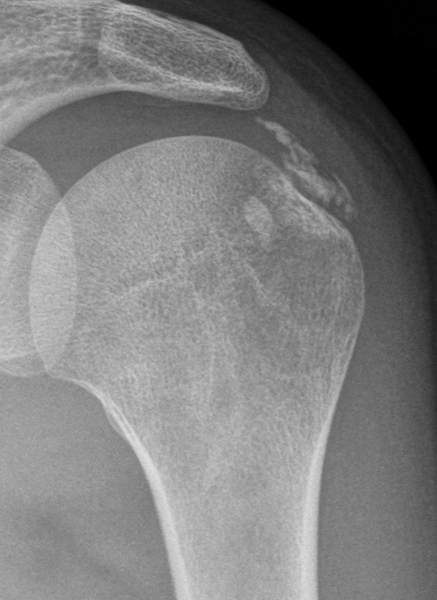

¿Qué ven ustedes en esa placa?

La placa es de hombro izquierdo, unos traumatólogos dicen fractura de troquíter o calcificación y otros descartan fractura... Aún no saben lo que tengo, me dicen que en la resonancia se vera.